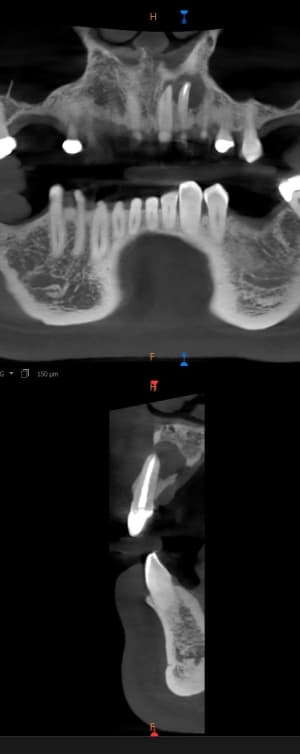

Capture d’écran 2025-09-08 à 17.34.45.png